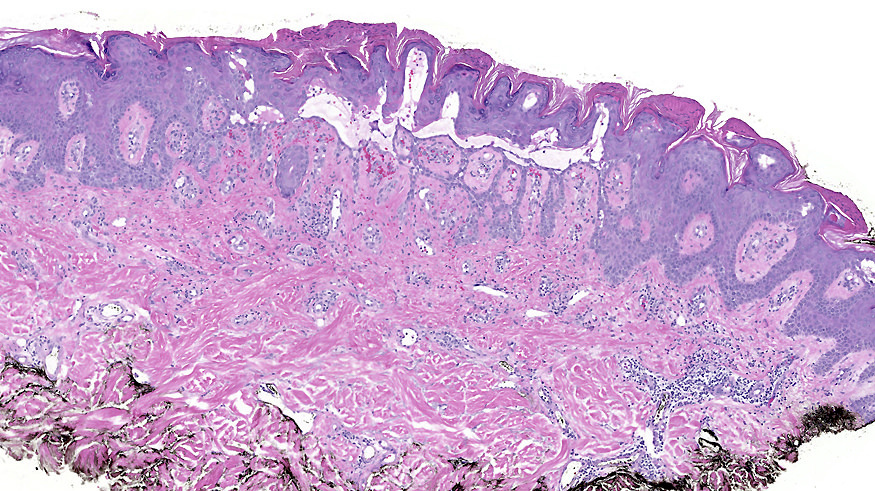

Microscopic (histologic) description

- Suprabasal acantholysis with vesicle formation is the principal microscopic finding

- Elongation of rete ridges with focal acantholysis and eosinophils may be the only early changes in Grover disease

- Main 4 histopathological patterns are:

- Pemphigus vulgaris / foliaceous-like: predominantly limited to suprabasal acantholysis, with basal keratinocytes attached to basement membrane forming a characteristic tombstone appearance

- Darier-like: suprabasal acantholysis of keratinocytes with scattered apoptotic or dyskeratotic cells within various levels of the epidermis

- Spongiotic: edema within epidermis, causing separation of keratinocytes and prominent intracellular bridges

- Hailey-Hailey-like: suprabasal acantholysis of all levels of the epidermis without significant dyskeratosis (dilapidated brick wall appearance)

- More than one pattern can be seen in the same setting

Microscopic (histologic) images